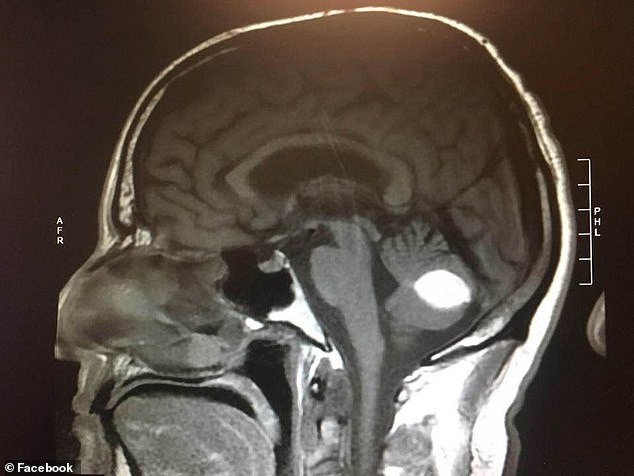

A páciens tervezett agyműtéte előtti napon ismét felvételt készítettek a koponyájáról – és semmi nyomát nem találták betegségnek.

Nem sokkal később a daganat teljesen eltűnt.